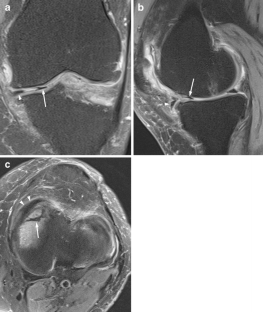

A total of 914 consecutive exams from 875 patients (524 men; mean age, 35 years) were reviewed. Vacuum phenomenon was found in 12 patients (prevalence 1.3%). In six (50%) patients, VP mimicked a meniscal tear, with four cases simulating a torn medial discoid meniscus. The VP signal was not easily differentiated from meniscal signal on most sequences in most cases (9/12). Gradient-recalled echo (GRE) localizer images proved most definitive, with 3D SPACE images the next most effective. Fast spin echo (FSE) images were only occasionally able to differentiate VP from meniscus.

Rarely recognized on MR, VP can mimic meniscal pathology, potentially leading to inappropriate surgery. Because differentiation of VP from the meniscus is challenging on FSE at 3 T, radiologists should become familiar with the appearance of VP and review GRE localizer or 3D images carefully to avoid misinterpretation.